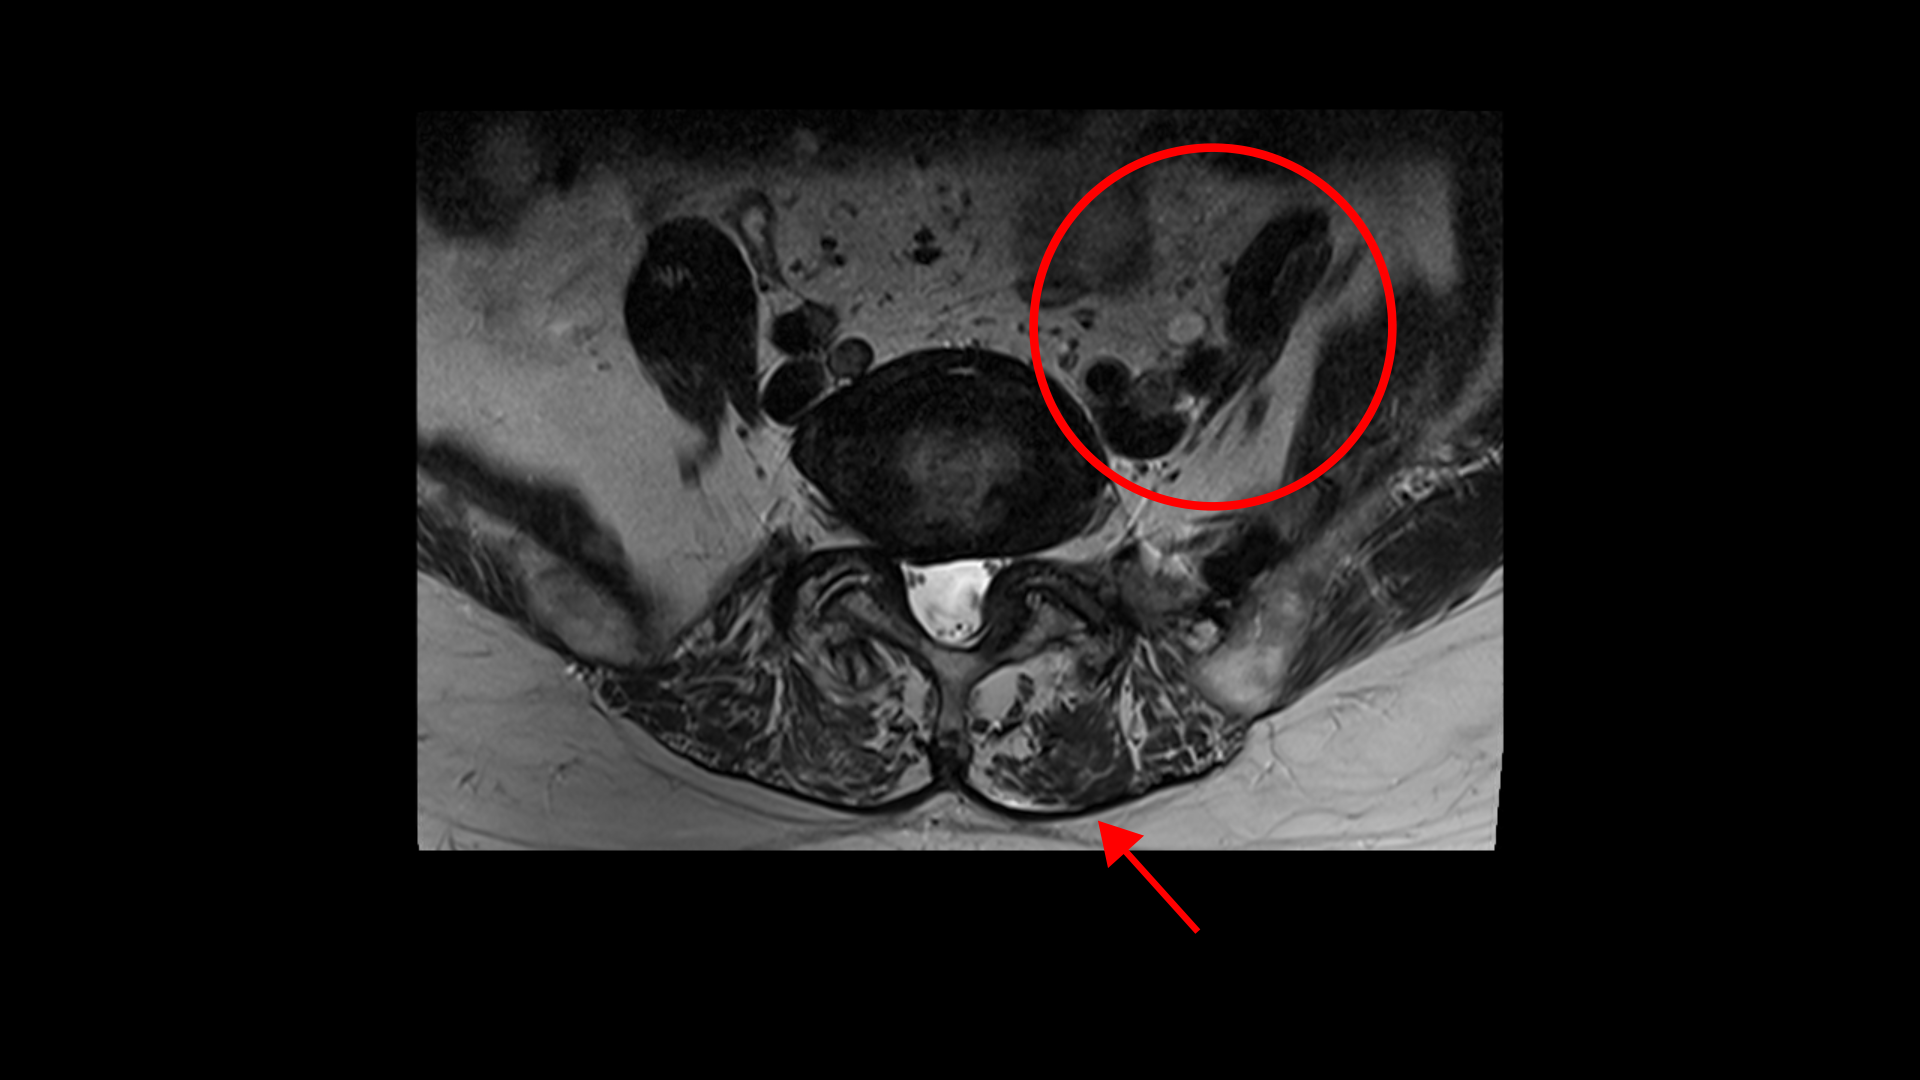

이 환자분의 근육을 MRI에서 보면 5번, 1번 마디에서 기립근과 장요근을 체크해봤을 때 기립근의 지방화 정도도 심하고 장요근, 특히 왼쪽 장요근은 거의 형체를 알아보기 어려울 정도로 위축이 심한 상태입니다.

그런데 저희 모커리한방병원은 신경 만이 문제가 아니고 오히려 80세가 넘어갈수록 신경보다 근육 문제가 훨씬 더 중요하다고 말씀 드립니다. 신경구멍이 좁아지는 속도보다 70대 이후 80세가 넘어가면서 근육이 줄어들고 망가지는 속도가 훨씬 더 빠르다고 말이죠. 특히 신경이 자극 받고 눌리는 상태에서는 근육이 위축되고 빠지는 속도가 더 빨라집니다.

협착증 환자분들의 나이가 70대, 80대가 넘어갈수록 근육은 점점 빠르게 줄어들고 방사통은 엉덩이와 다리 근육의 심한 위축을 가져옵니다. 이렇게 근육이 빠지고 근육 기능이 망가지면 근육이 허리를 잘 지탱하지 못하기 때문에 신경 눌림이 더 심해지는 겁니다. 또, 근육 자체의 문제로 인한 근육에서 발생하는 만성적인 통증과 힘 빠짐도 심해지구요. 그래서 해가 갈수록 심해지는 통증과 증상들을 신경의 문제로만 생각하는 분들이 계신데 70에서 80세를 넘어갈수록 사실은 근육의 문제가 오히려 더 심해집니다. 그래서 근육을 치료해서 근육이 좋아지는 만큼 협착증 환자분의 증상도 함께 좋아지는 거구요.